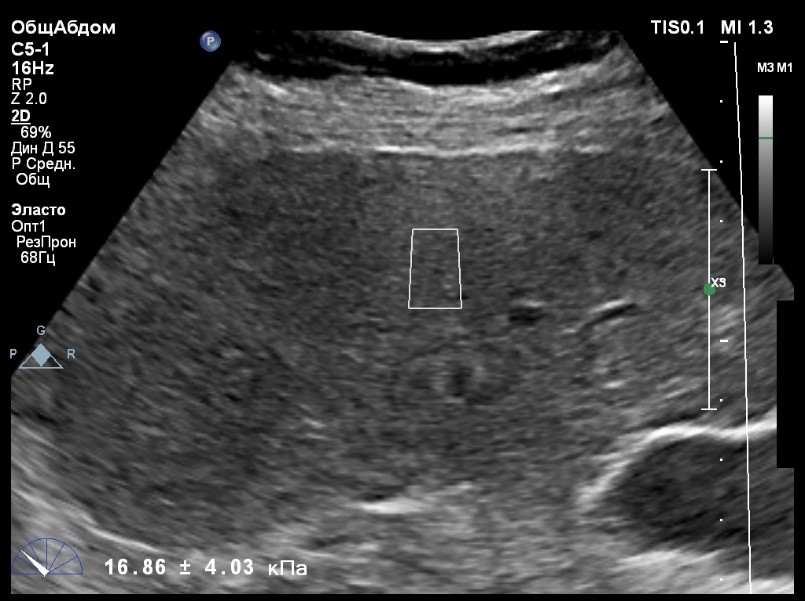

Пациент обратился к доктору с направлением на исследование степени жесткости печени в ноябре 2017 года. Из истории болезни, пациент страдает Гепатитом С с 2002 года. Закончила противовирусное лечение в мае 2017 года. В сентябре 2016 года, с помощью транзиентной эластографии была установлена медиана жесткости печени 45 kPA. На момент настоящего исследования, пациент не принимал пищу на протяжении 4 часов, АСТ, АЛТ не превышают патологических значений. В виду технических сложностей выполнения исследования (узкие межреберные промежутки), для оценки жесткости была выбрана технология компании Philips ElastPQ (точечная эластография) и прибор компании Philips Epiq 7. Исследование было проведено в соответствии с клиническими рекомендациями для ультразвуковых приборов компании Philips. В результате исследования были получены следующие результаты:

| 1 [17.28] kPa | 2 [13.59] kPa | 3 [14.47] kPa |

| 4 [16.71] kPa | 5 [18.48] kPa | 6 [21.20] kPa |

| 7 [21.36] kPa | 8 [15.64] kPa | 9 [19.95] kPa |

| 10 [19.89] kPa | 11 [22.14] kPa | 12 [16.48] kPa |

| 13 [16.41] kPa | 14 [22.02] kPa | |

Стандартное Отклонение [2.75] kPa Медиана Жесткости [17.88] kPa Фактор Качества IQR/Med 9%

Зона интереса расположена на более чем на один сантиметр глубже капсулы, параллельно ходу луча, в середине изображения, в участке печени лишенном артефактов.

Капсула видна как белая линия перпендикулярная ходу ультразвукового луча, исследования производятся приблизительно в одном и том же сегменте печени.

Для интерпретации полученных клинических данных были использованы Рекомендации по проведению эластографии сдвиговой волной для оценки жесткости печени при использовании ультразвуковых аппаратов компании Филипс с примером протокола. Следует отметить достаточно высокую жесткость печени у пациента по данным предыдущих обследований и низкую активность основного заболевания по данным биохимических проб, что является показанием для динамического наблюдения и оценки жесткости печени. Отмечу, что для проведения исследования у данного технически сложного пациента был совершенно обоснованно выбран аппарат экспертного класса. Подготовка пациента соответствовала проводимому исследованию. Представленные слайды проведенного исследования свидетельствуют о правильном техническом исполнении проб, что позволяет заключиться о достоверности полученных измерений. Таким образом, учитывая полученную медиану жесткости на уровне 17,88 кРа (13.59 -22.02 kPa) и уровень стандартных отклонений не превышающих 30%, полагаю, что уровень степени фиброза соответствует стадии F4. Заведующий отделением УЗД МЦ «Асклепий», Глушенко Д. Е.